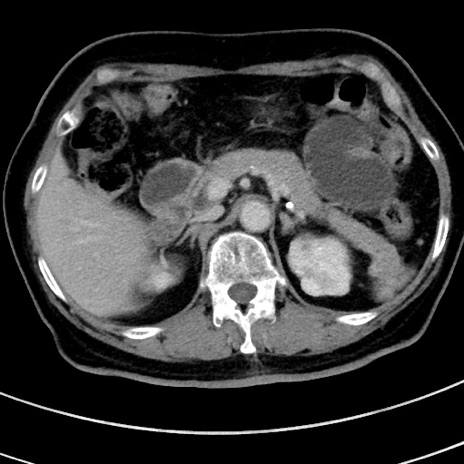

症例

冠状断像